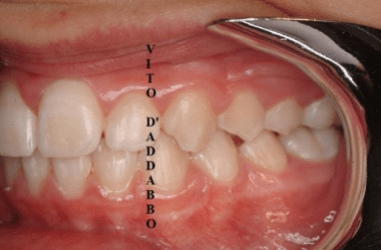

In una bocca che chiude correttamente i denti dell’arcata superiore sono collocati più esternamente rispetto ai corrispondenti dell’arcata inferiore. Nel morso inverso accade il contrario: in quello laterale sono i denti inferiori laterali a chiudere esternamente.

Questa malocclusione è il più delle volte dovuta a un mascellare piccolo, come nel caso riportato, dove manca anche lo spazio per l’incisivo laterale permanente di sinistra. I morsi incrociati vanno corretti precocemente perché possono provocare gravi asimmetrie del viso.

prima